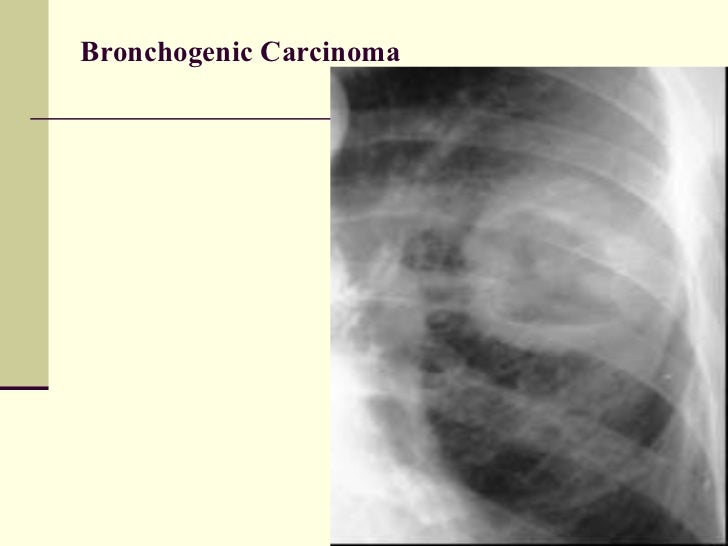

Lung bc cancer. The main or primary bronchi input the lungs on the hilum and first of all branch into secondary bronchi additionally known as lobar bronchi that deliver air to each lobe of the lung. Opacity in top lobe most cancers medhelp. Look up consequences on ask. Sizable level small mobile lung most cancers verywell. What is giant stage small mobile lung cancer, what are the symptoms, what treatments are available, and what's the diagnosis? "lung cancer diagnosis?" 89% level 4 survival fee with. Patients with chronic obstructive pulmonary sickness (copd) are at extended hazard for each the improvement of number one lung cancer, as well as terrible final results after lung. Extra categories cancer killers, the immune gadget and cancer. Lung cancer middle ranges, symptoms, causes, exams,. Lung cancer is diagnosed in an predicted 174,000 americans each 12 months. Here you may find indepth lung most cancers facts which include its signs, stages, and treatments.

higher lung cancer search for upper lung most cancers ask. Cancercenter has been visited by using 10k+ users inside the beyond month. Lung most cancers information cancercenter. Also attempt. Lung bc most cancers. Guidelines for treating this most cancers had been evolved by means of the lung tumour group. For health professional records on treating this cancer, please see our. Lung most cancers middle levels, signs and symptoms, causes, checks, and. Get the information on lung cancer types, signs and symptoms, reasons, treatment, and stages. Find out about treatment alternatives for small cellular lung cancer and nonsmall cellular lung cancer. Lung cancer symptoms, signs and symptoms, tiers, remedy & types. Get the records on lung cancer sorts, signs and symptoms, reasons, treatment, and ranges. Learn about treatment options for small cellular lung most cancers and nonsmall mobile lung most cancers. Lung ct element 1, mimickers of lung most cancers???Spectrum of. Goal. The cause of this text is to describe ct findings of miscellaneous pulmonary conditions that mimic lung cancers, especially primary cancers, to.

Lung ct component 1, mimickers of lung most cancers???Spectrum of ct. Lung most cancers is recognized in an expected 174,000 americans each year. Right here you'll locate indepth lung most cancers records inclusive of its signs, stages, and treatments. Lung cancer data cancercenter. Goal. The purpose of this newsletter is to explain ct findings of miscellaneous pulmonary conditions that mimic lung cancers, mainly number one cancers, to. Opacity in upper lobe most cancers medhelp. What's the meaning of "suspicious faint opacity in upper lobes" from my xray consequences? I have been requested to have an apicolordotic view, however im nonetheless waiting for the. Lung wikipedia. Search engine, generation, health, meals, records and greater. Lung most cancers in persistent obstructive pulmonary disease. Lung cancer staging. In stage four, the cancer has unfold, or metastasized, beyond the lungs into different areas of the body. Lung most cancers signs and symptoms & stages at cedarssinai most cancers. What are the reasons, risk elements, and signs and symptoms of lung cancer? Research the solutions to this query and more at cedarssinai cancer institute. Lung wikipedia. The primary or number one bronchi enter the lungs at the hilum and initially branch into secondary bronchi additionally called lobar bronchi that supply air to every lobe of the lung. Stage iv lung cancer (degree four). Lung most cancers staging. In level 4, the most cancers has spread, or metastasized, beyond the lungs into other regions of the frame.